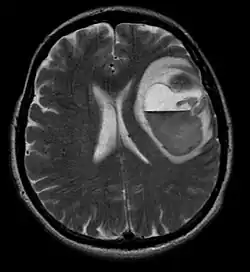

La tomodensitométrie (TDM) et L'imagerie par résonance magnétique (IRM) peuvent détecter efficacement une néoplasie dans le cerveau. L'IRM est plus sensible que la TDM pour identifier les lésions, mais présente des contre- indications pour les patients porteurs de stimulateurs cardiaques, de prothèses incompatibles, de clips métalliques et contre-indications. La TDM reste la méthode de choix pour détecter les calcifications au sein des lésions ou les érosions osseuses de la calotte ou de base du crâne. L'utilisation d' agents de contraste, iodés dans le cas du scanner et paramagnétiques (gadolinium) dans le cas de l'IRM, permet l'acquisition d'informations sur la vascularisation et l'intégrité de la barrière hémato-encéphalique, une meilleure définition de la tumeur tumorale par rapport à l' œdème environnant et à la génération d' hypothèses sur le degré de malignité. L'examen radiologique permet également d'évaluer les effets mécaniques et les modifications importantes des structures cérébrales résultant de la tumeur, telles que l' hydrocéphalie et les hernies, dont les effets peuvent être fatals. Enfin, en préparation à la chirurgie, ce diagnostic peut être utilisé pour déterminer la localisation de la lésion ou l'infiltration de la tumeur dans des zones vitales du cerveau. À cette fin, l'IRM est plus efficace que la tomodensitométrie car elle peut fournir des images en trois dimensions.

Les outils d'imagerie radiologique diagnostique mettent en évidence la modification du tissu néoplasique par rapport au parenchyme cérébral normal (par le biais de modifications de la densité tissulaire imagée électroniquement en TDM et de l'intensité du signal en IRM). Comme la plupart des tissus pathologiques, les tumeurs sont également reconnaissables par une accumulation accrue d'eau intracellulaire. Dans la tomodensitométrie, ils apparaissent hypodenses, c'est-à-dire de moindre densité que le parenchyme cérébral, dans la tomographie par résonance magnétique nucléaire avec relaxation spin-réseau hypointense et en relaxation spin-spin ainsi que l' hypersignal en pondération protonique (PD).

La zone saine du cerveau ne doit présenter aucune luminescence particulière sur une image radiologique. Par conséquent, il va sans dire que l'attention est portée sur des plages de signaux de contraste plus larges.

Dans le tissu tumoral, en général, la plus grande proportion d'amélioration du contraste est due à la barrière hémato-tumorale particulière qui permet le passage de l'iode (CT) et du gadolinium (IRM) dans l'espace interstitiel extravasculaire intratumoral. Cela augmente le signal (densité ou intensité) de la tumeur. Cependant, des précautions doivent être prises pour s'assurer que l'amélioration du contraste ne différencie pas définitivement la néoplasie de l'œdème péri-lésionnel. En fait, la découverte anatomo-pathologique dans le tissu tumoral infiltrant malin du gliome, comme dans le glioblastome et l'astrocytome anaplasique, montre également au-delà de l'œdème vasogénique causé par la destruction de la barrière hémato-encéphalique par la tumeur. Cette dernière condition clinique est difficilement détectable par imagerie diagnostique.

La tomodensitométrie du cerveau montre généralement une masse tissulaire qui peut être améliorée par l'un ou l'autre contraste. Au scanner, les gliomes de bas grade apparaissent généralement isodenses au parenchyme normal et peuvent donc ne pas présenter de rehaussement de contraste. De même, les lésions de la fosse crânienne postérieure sont difficiles à identifier au scanner. Par conséquent, les seuls résultats d'une telle tomographie ne sont pas toujours suffisants à des fins diagnostiques. Dans les cas douteux, l'utilisation de l'imagerie par résonance magnétique plus sensible est indispensable.

Sur-L'IRM montre une tumeur intracrânienne comme une lésion massive qui peut devenir plus luminescente après utilisation du produit de contraste. Cependant, il y a toujours une anomalie de signal dans -L'imagerie par résonance magnétique, qui indique la présence d'une néoplasie ou d'un œdème vasogénique. Habituellement, une luminescence accrue (amélioration du contraste) indique une tumeur d'un grade supérieur de malignité. Un anneau de contraste est caractéristique du glioblastome, avec la partie luminescente correspondant à la partie vitale de la tumeur maligne, et la plus foncée - zone hypointense correspondant à une nécrose tissulaire.